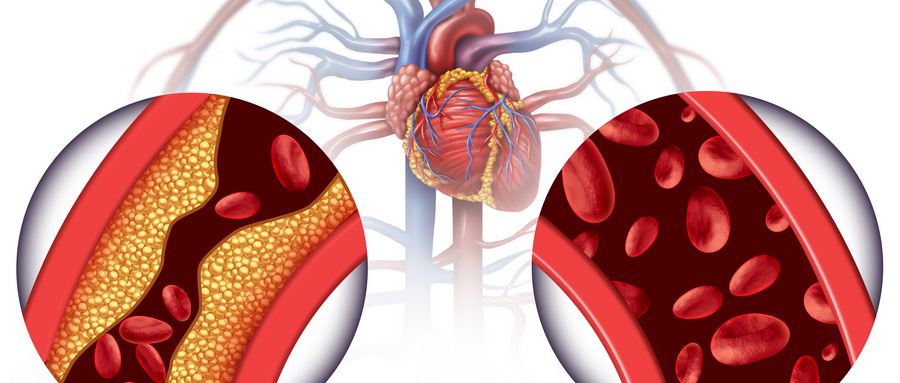

- 冠心病、心绞痛;

- 高血压、高血脂;

纽约法拉盛心脏病医生治疗各类心血管疾病